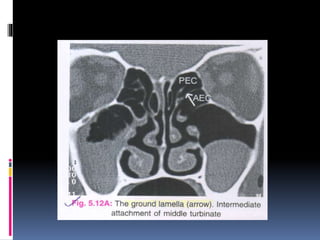

 The middle turbinate is attached to lamina

papyracea by its ground lamella.This

lamella separates anterior ethmoid cells

from posterior ethmoid cells.